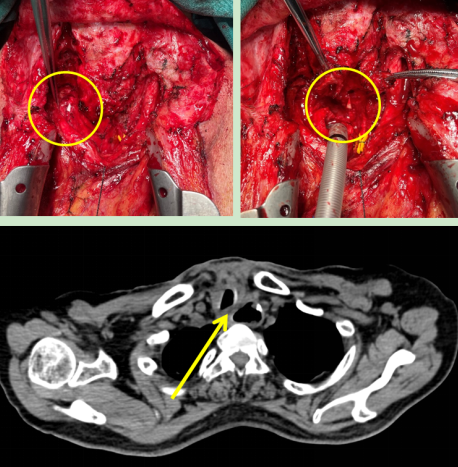

圖2:術(shù)中情況(左)喉返神經(jīng)監(jiān)測(cè)儀監(jiān)測(cè)喉返神經(jīng),(右)離斷氣管暴露食管瘺口;

(下)術(shù)后CT顯示原氣管食管間瘺口已修補(bǔ)。

在與患者及家屬充分溝通后,胡楊團(tuán)隊(duì)為患者行“經(jīng)頸部及正中開(kāi)胸氣管食管瘺修補(bǔ)術(shù),胸大肌帶蒂肌瓣轉(zhuǎn)移成形術(shù)”。術(shù)中使用喉返神經(jīng)監(jiān)測(cè)保護(hù)喉返神經(jīng),使用帶蒂胸大肌肌瓣隔絕氣管與食管間瘺口。手術(shù)順利完成,術(shù)后患者未發(fā)生聲音嘶啞。

術(shù)后第五天,患者突然出現(xiàn)頸部皮下氣腫,經(jīng)檢查是因?yàn)橹霸和馐中g(shù)形成的瘢痕,導(dǎo)致氣管缺血壞死,出現(xiàn)氣管吻合口瘺。這是多次手術(shù)的患者術(shù)后可能出現(xiàn)的問(wèn)題之一,處理極其困難,若處理不當(dāng)極易造成慢性胸骨感染,甚至威脅生命。胡楊副主任醫(yī)師立馬安排第二次手術(shù),術(shù)中使用另一側(cè)帶蒂胸大肌肌瓣修補(bǔ)并加固了氣管瘺口,術(shù)后復(fù)查顯示氣管瘺口成功修補(bǔ)。